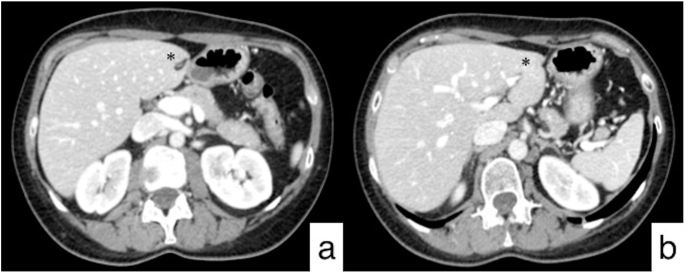

Fig. 2.

Follow-up CT performed after second line treatment. Axial CT images (a, b) show the complete disappearance of the lesions in the left hepatic lobe (black asterisk).